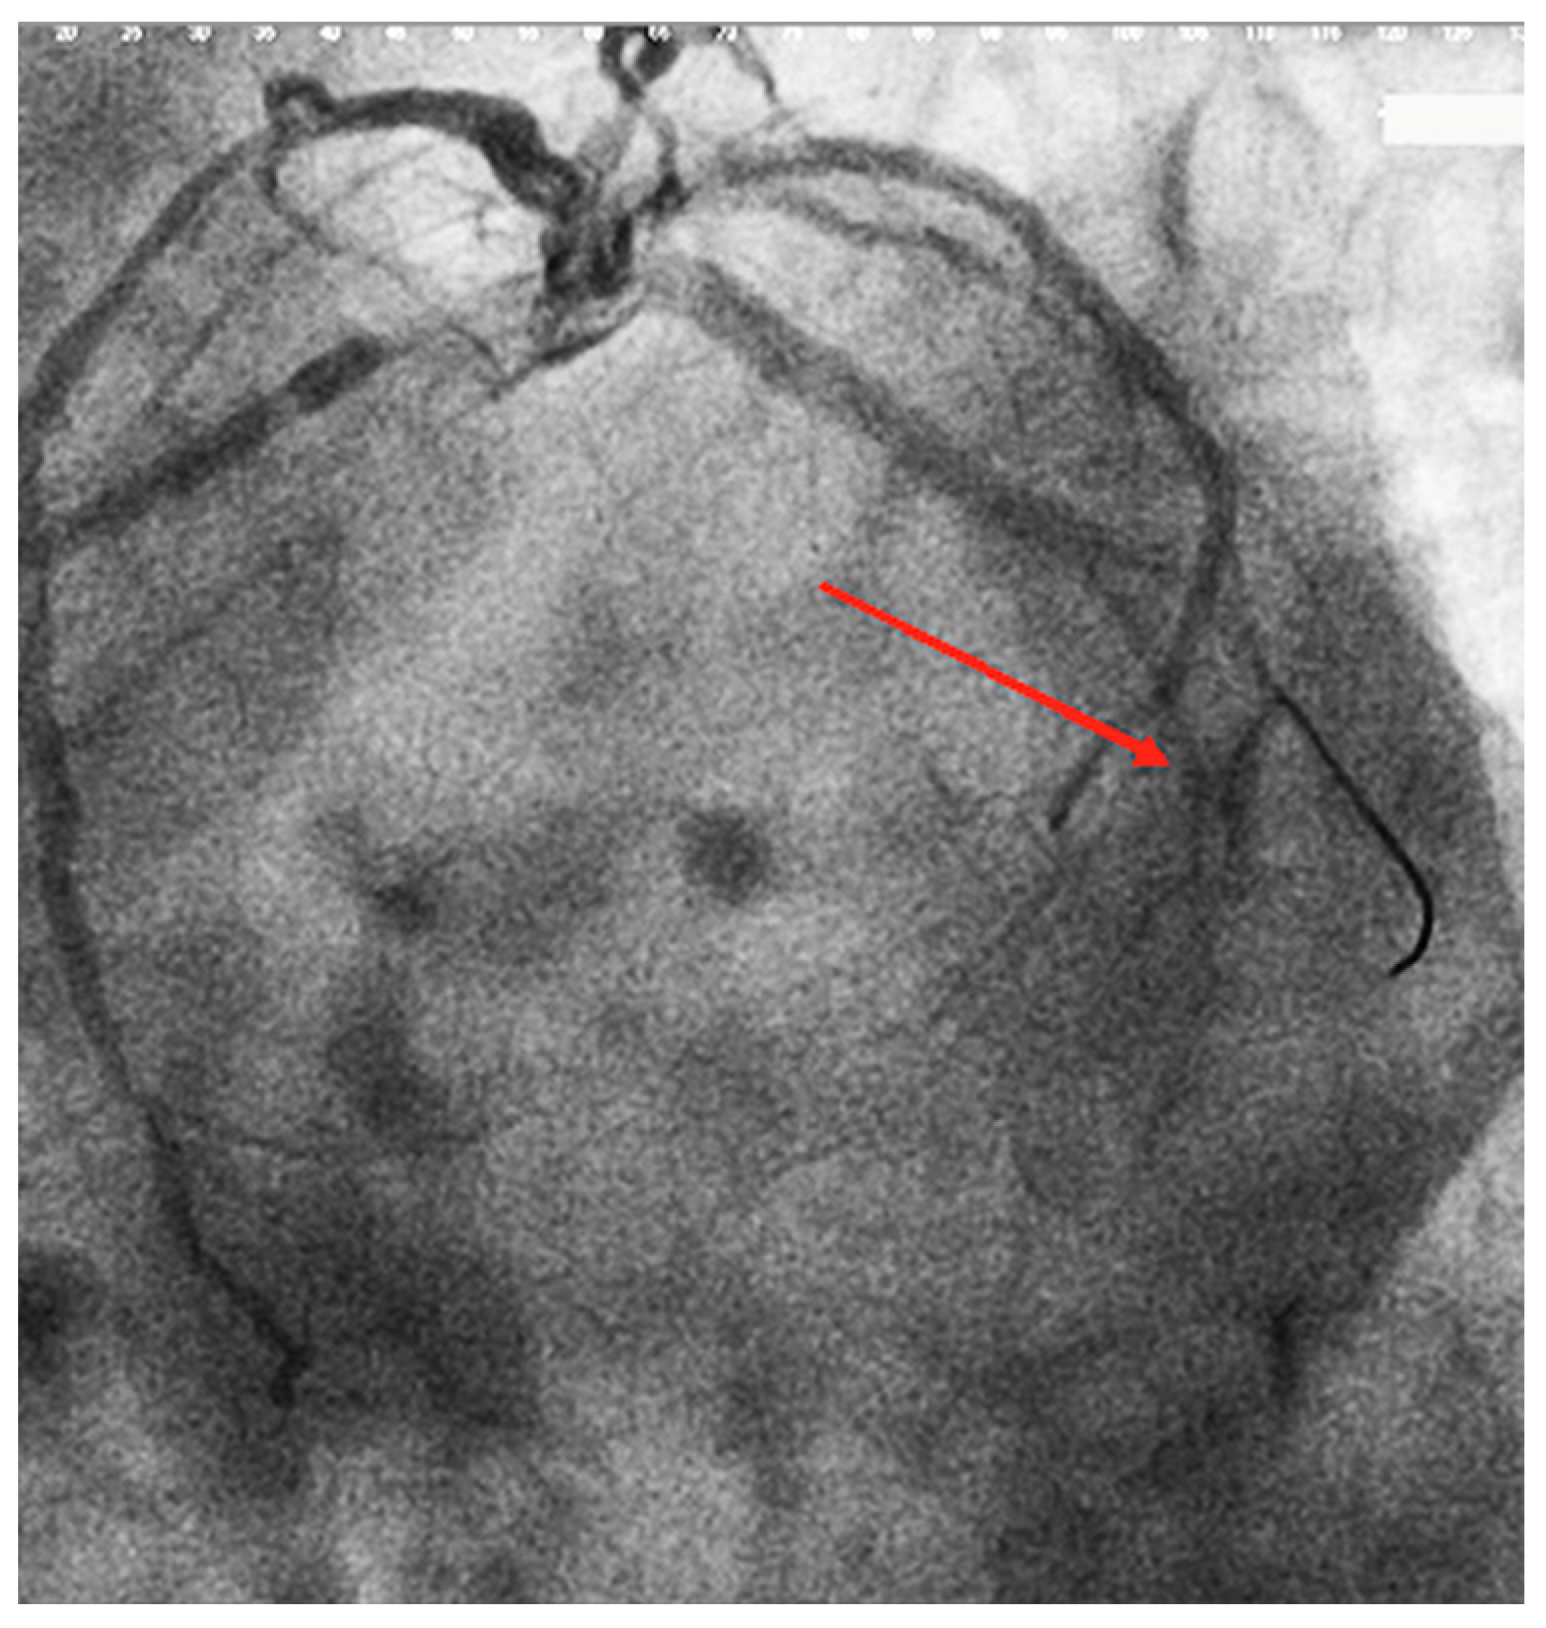

5.1.2. Coronary Angiography

TIMI Flow Grade

CTFC

MBG

TMPG